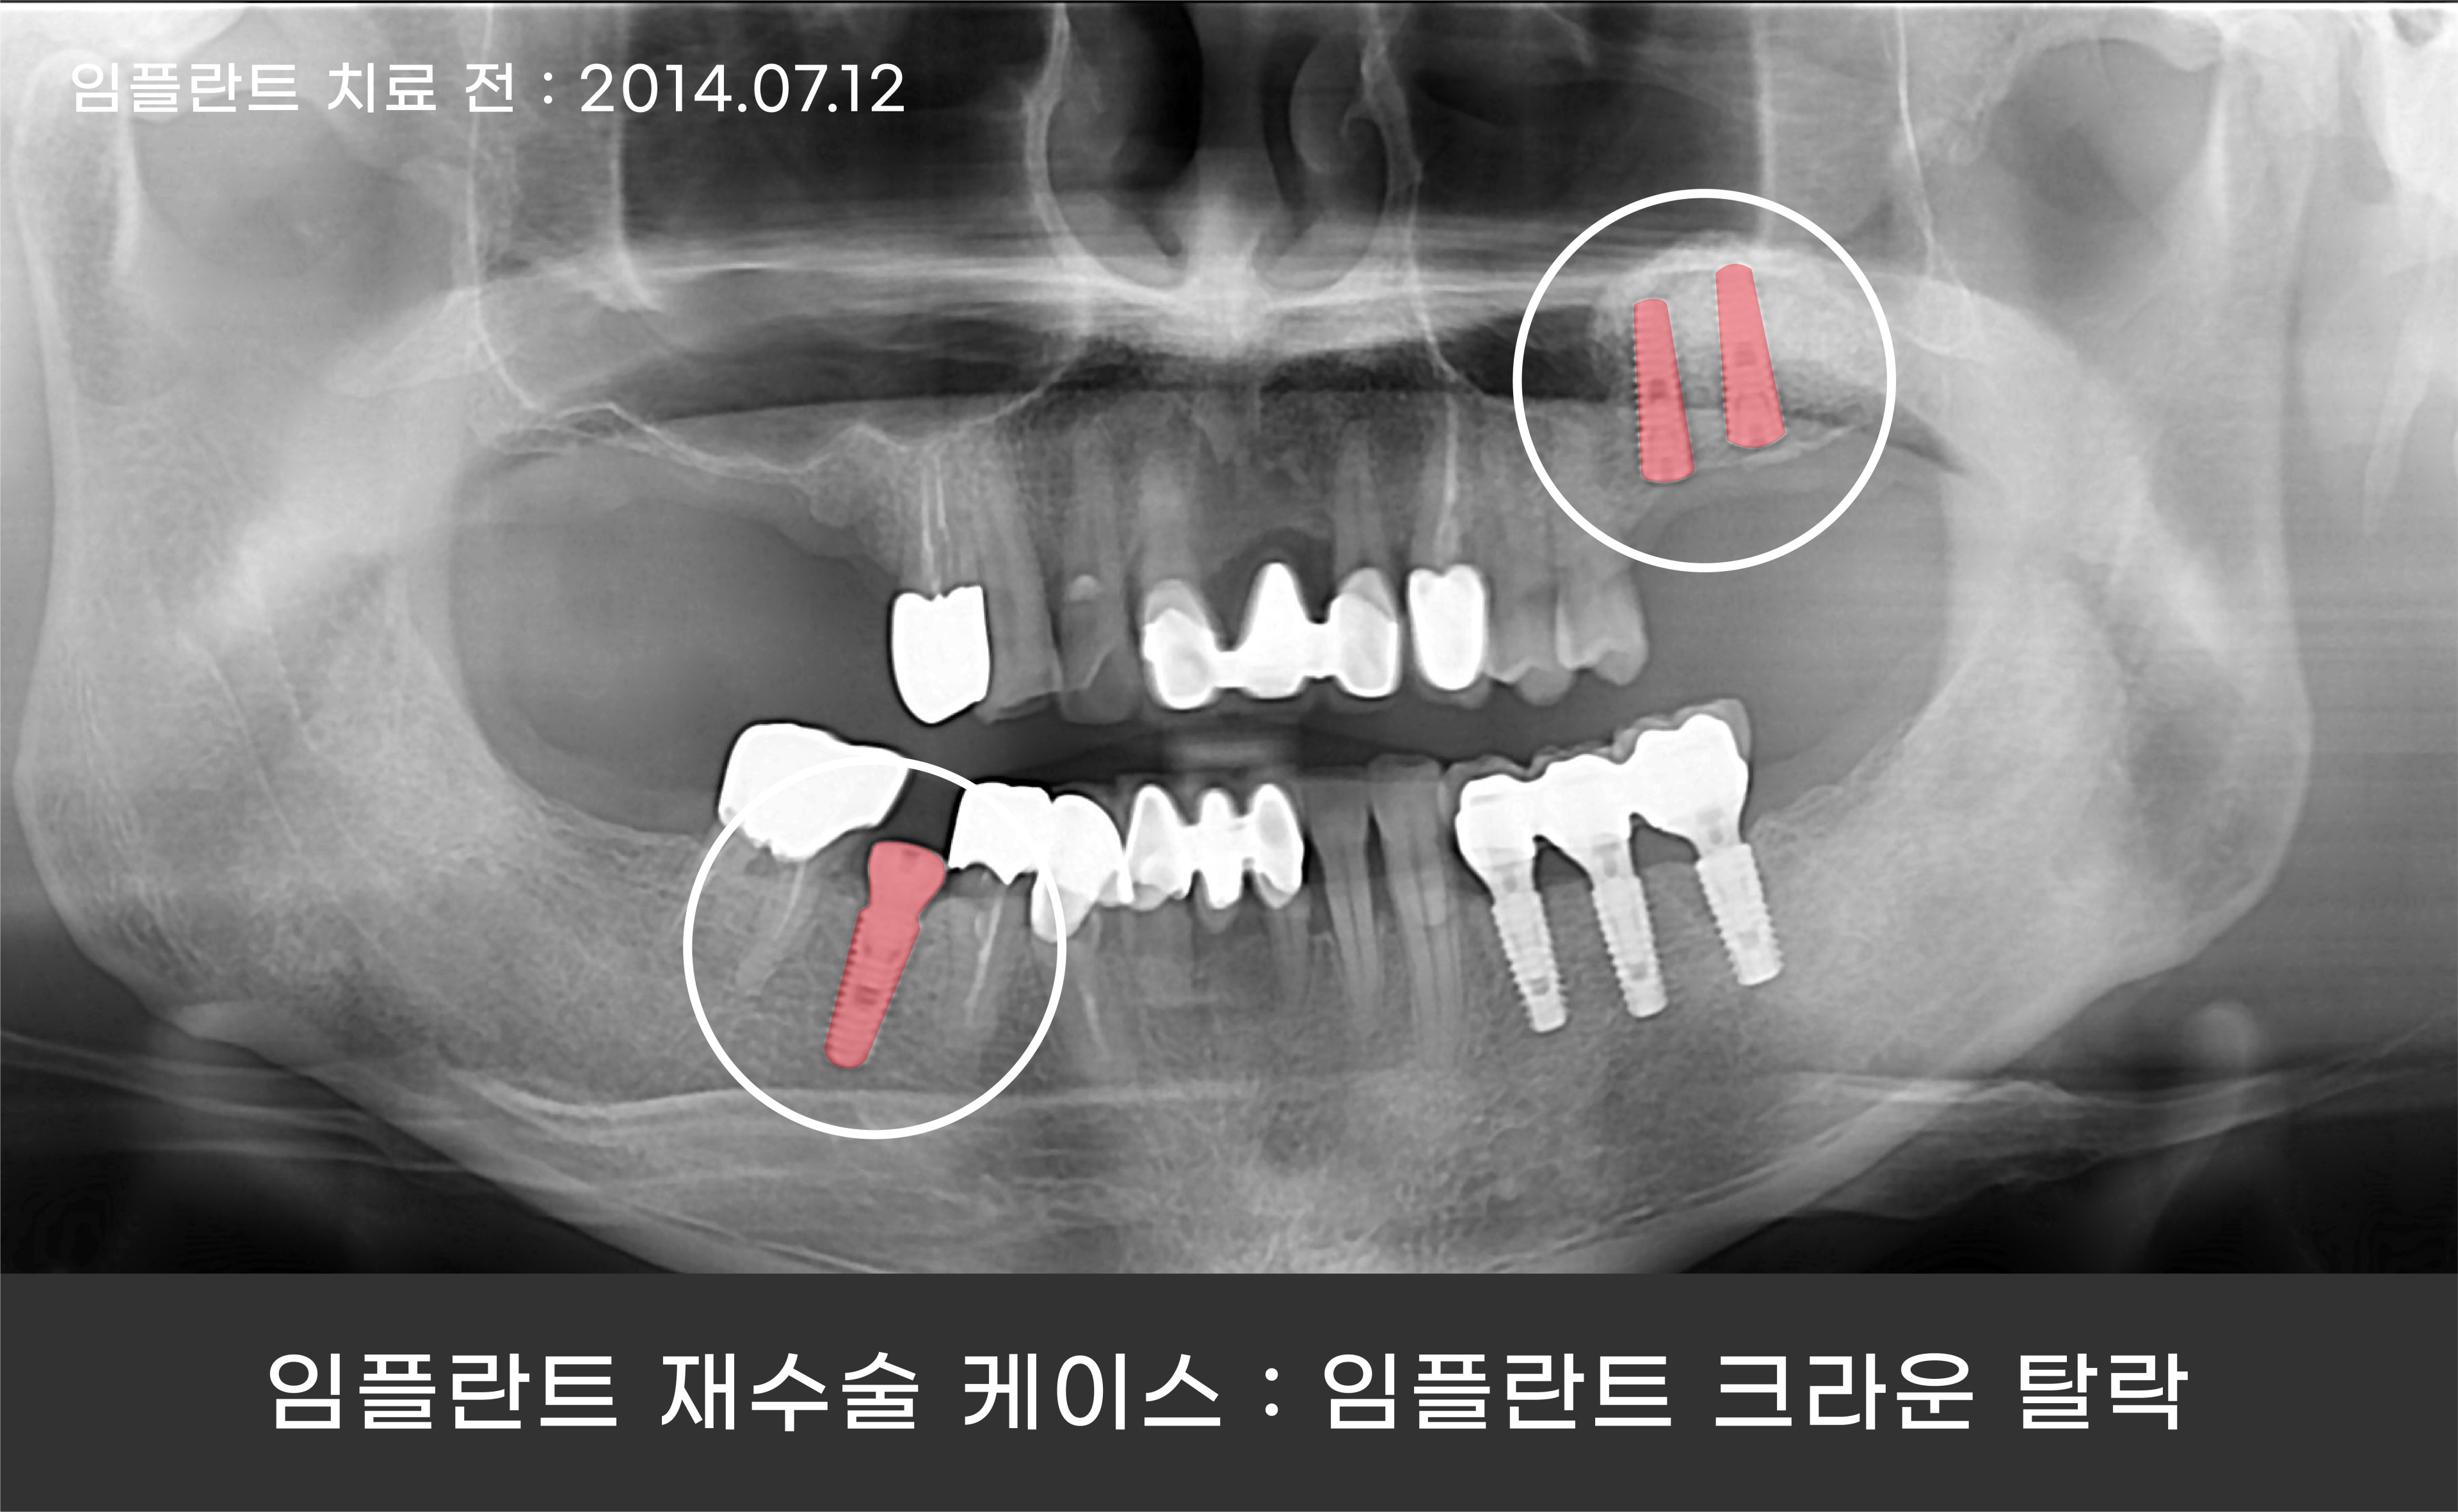

환자분의 경우에는 임플란트 크라운의 탈락으로 내원해 주셨는데요.

임플란트 크라운이 손상되는 대부분의 원인은 질기고 단단한 음식을 자주 섭취하거나

이 악무는 습관, 이갈이 등 임플란트에 가해지는 충격이 누적되면서 크라운이 깨지거나

빠지게 됩니다.

이러한 습관은 임플란트 보철에 좋지 않은 영향을 끼칩니다.